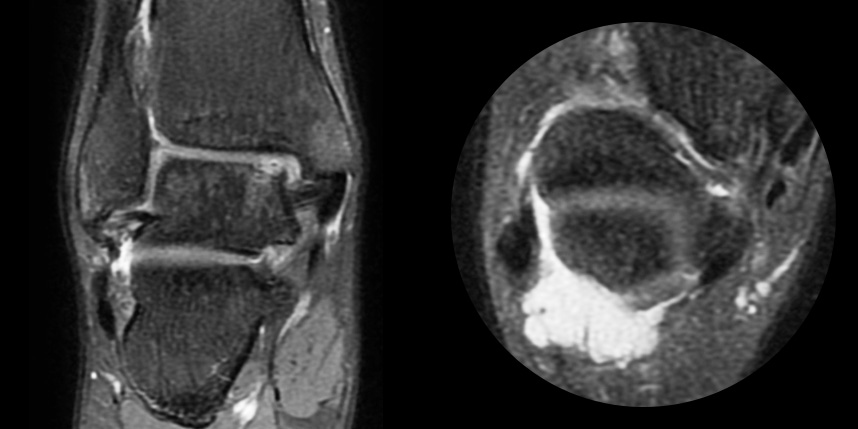

환자 자신의 건강한 연골을 채취하여 손상된 부위에 이식하는 방법으로, 발목 연골 손상에 주로 이용하며 정상 연골을 채취해야 하기 때문에 공여부(donor site)의 문제가 있을 수 있다는 점이 최대 단점입니다.

동종 제대혈줄기세포를 이용하여 연골 재생을 촉진하는 방법으로 초자연골에 가까운 연골로 재생되는 것을 기대할 수 있습니다.

본원에서는 미세천공술, 콜라겐주입술, 카티스템 치료를 주로 하고 있습니다.

연골 손상이 크거나 작고 어느 위치에 있어도 연골재생술이 가능합니다.

연골재생술 진행

(미세천공술 + alpha)

타병원 미세천공술 실패 후 통증으로 내원하신 사례